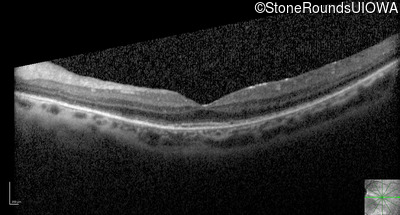

Optical Coherence Tomography - Right - 20/50 -1

Exemplar / OCT Stack

Optical Coherence Tomography - Left - 20/40 -2